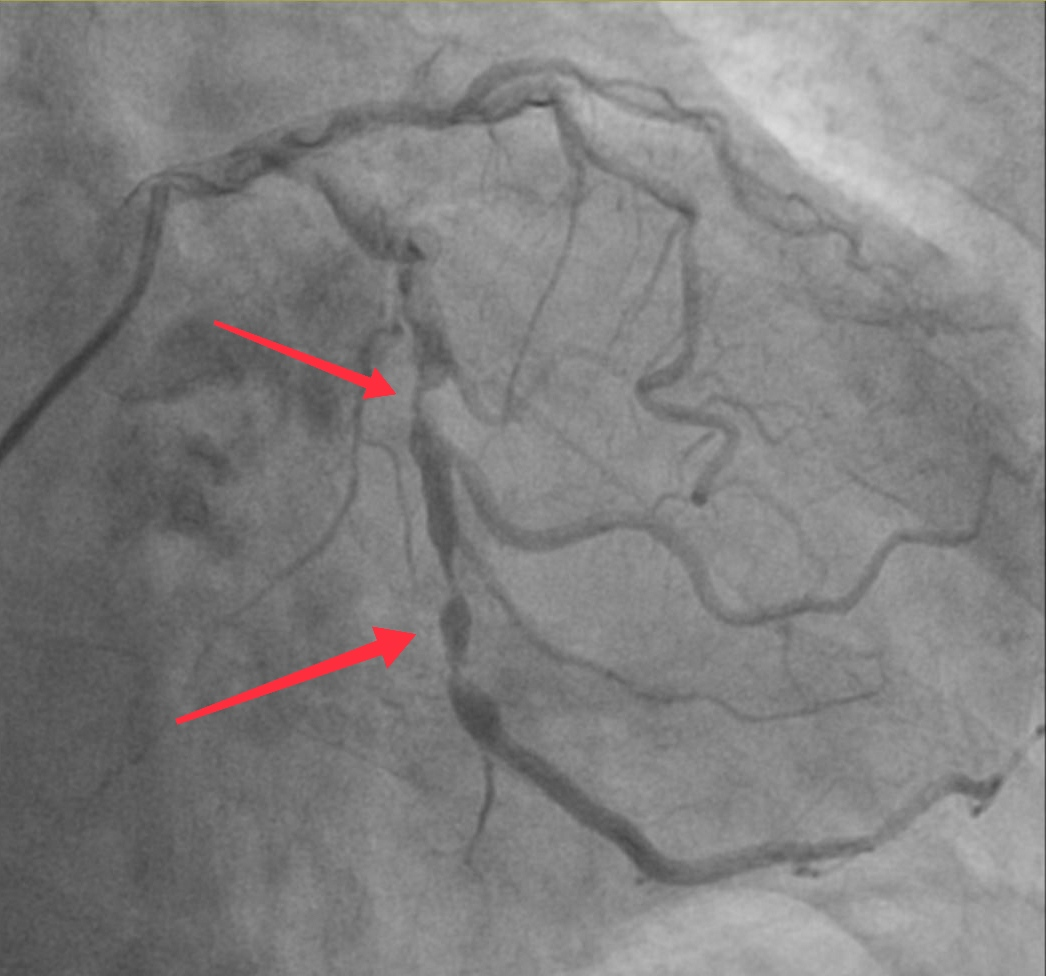

杨嗲嗲既往有“肺气肿”、“颈动脉粥样硬化”、 “胆囊结石”、 “前列腺增生”等病史。心脏彩超显示主动脉瓣钙化、重度狭窄并返流,冠脉影像显示冠状动脉病变也很严重。

冠脉造影,红色箭头提示冠脉左回旋支严重狭窄